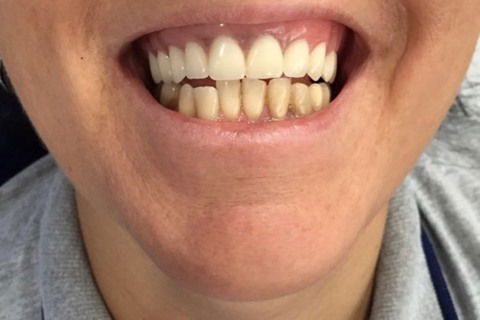

Paciente com síndrome de kelly,foi feito exodontia do 33 ao 43,regularização da tábua óssea e colocação de 5 implantes Implacil UN2 cônicos HI de 4x12,em seguida foi feito procedimento protetitico.